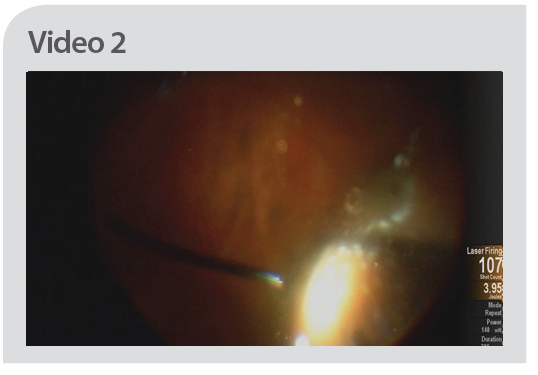

360° SCLERAL-DEPRESSED PERIPHERAL LASER TREATMENT DURING RETINAL DETACHMENT SURGERY

Use of 360° scleral-depressed peripheral laser treatment may reduce the likelihood of patients developing peripheral retinal detachment from newly formed breaks during the postoperative period (Video 2). Ideally, laser should be applied from the posterior edge of the ora to the posterior edge of the anterior vitreous base (which is typically the location of the most posterior break). Light laser burns with short duration (200 ms) are applied in a scattered, nonconfluent fashion for 360°, avoiding heavy laser burns. If possible, the horizontal meridians should be avoided to prevent lasering the ciliary nerves, thereby decreasing the likelihood of postoperative pupillary dilation. In phakic patients, the use of a curved or directional lighted laser probe may be necessary to perform this procedure. Tamponade with C3F8 gas and face-down positioning for around 1 week may help decrease the rate of postoperative redetachment.